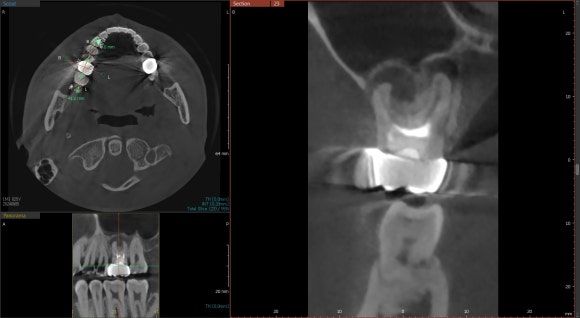

20250411

치료가 끝나고 6개월 정도가 경과했을 때,

정기검진을 위해 다시 내원하셨습니다.

뿌리 주위가 깔끔해진 것을 확인할 수 있습니다.